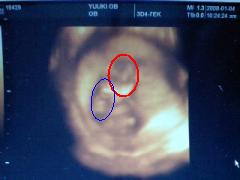

⑤超音波検診(白黒の画面とカラー?の二つで確認。今回もらった写真は↓)

意外とわかりにくーーい!!

←赤丸が顔です。こっちむいてます。

←青丸が右手なんだけどこっち向いて招き猫して

おいでおいでしてたよー

ここで心臓の音を聞かせてもらったり、ビデオまで撮影してもらいましたw

あ、赤ちゃんの大きさは

6.5センチ くらいだそう。

もっとおっきくなってるかとおもったけどそんなものか・・・。

でも確実に大きくなってるし元気に動いてたしw

順調みたいです